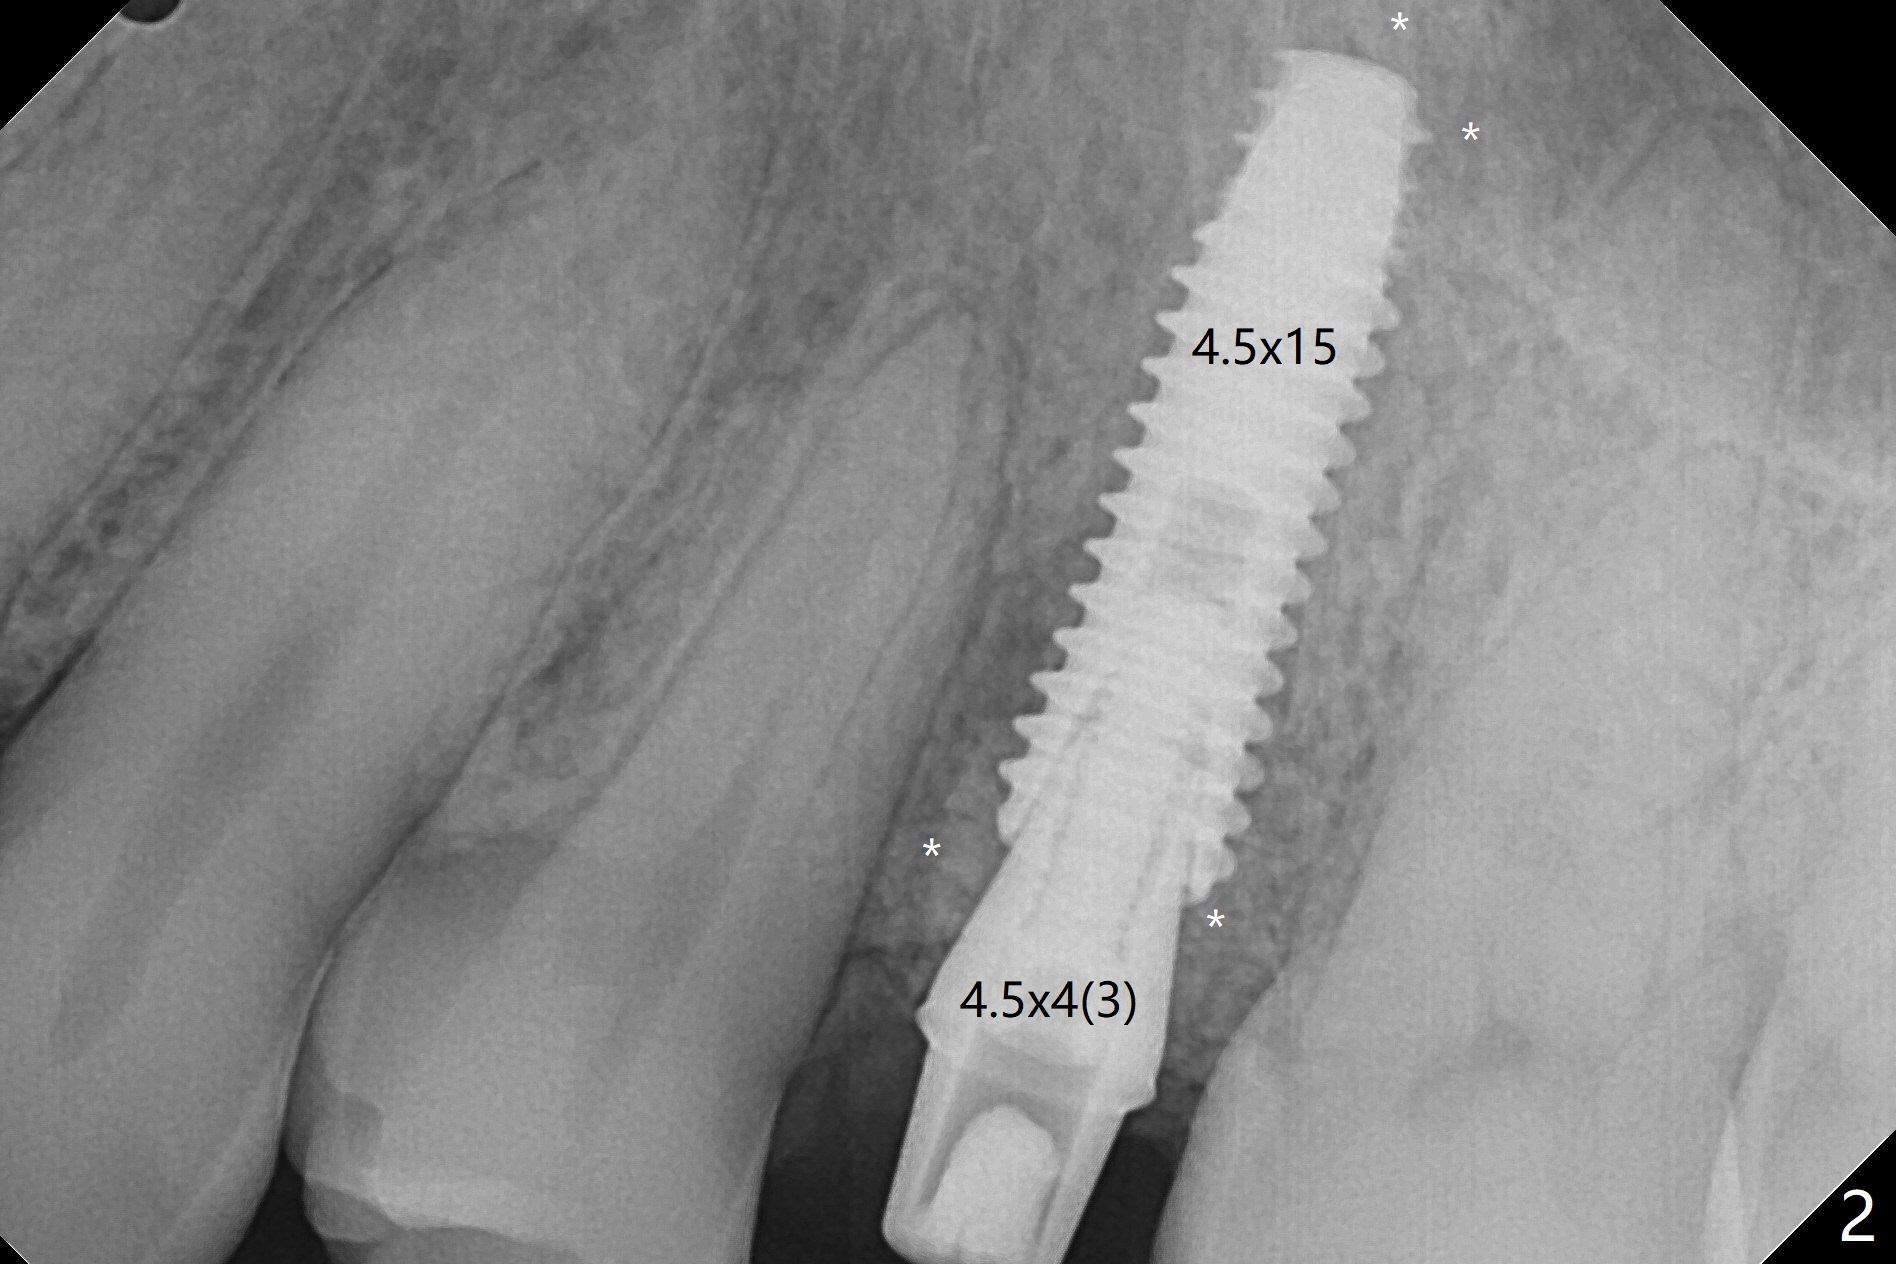

DIO lab refuses fabricating guide because of the large socket and recommends extraction and socket preservation at #13. Due to short apical bone (Fig.5,7), a long dummy implant (3.8x15 mm) is placed with periimplant space immediately post extraction (Fig.1 *). The final implant is larger (4.5x15 mm) with simultaneous sinus lift and periimplant bone graft (Fig.2,6,8 *). To repair the palatal crest defect (Fig.3 *) associated with tooth fracture (Fig.5 white dashed line), the implant is not placed too palatal with sufficient amount of the bone graft (Fig.4,6 *). The native bone (higher in bone density, Fig.9 white arrowheads, as compared to black one (for bone graft)) appears to have grown into the space between implant threads 5.5 months postop. The permanent crown/abutment is loose 1 year 9 months post cementation; after proximal reduction (Fig.10 arrowheads), the abutment is reseated completely. Pick up impression is taken and a healing abutment is placed. A few days later, the crown and abutment (separate) are seated passively; the abutment screw is retightened; the crown is re-cemented. The crown and abutment is removed for residual cement removal (Fig.11). Since there is mild buccal plate atrophy (Fig.11 B), the crown has a buccal lip (Fig.12 B) to prevent food impaction. The lip makes it difficult to remove residual cement intraorally. Therefore an access hole is necessary (Fig.13).